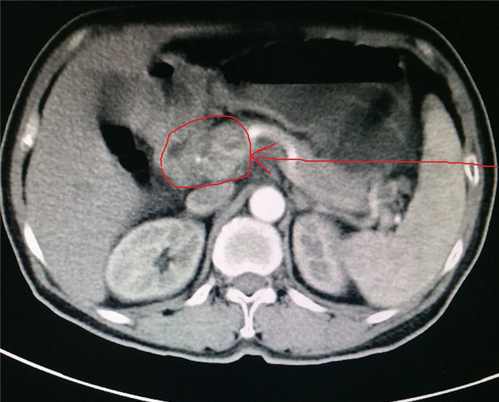

2017-07-07(治疗前)腹部强化CT:胃窦癌伴腹膜后、腹腔淋巴结转移,累及胰头,胰腺颈。